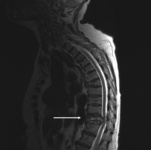

IRM de la columna torácica: vista sagital (secuencia ponderada en T2) con fractura patológica del cuerpo vertebral T10 causada por mieloma múltiple

De la colección personal del Dr. B. Nurboja y D. Choi

Ver esta imagen en el contexto de la/s siguiente/s sección/es:

Traumatismo de la columna toracolumbar